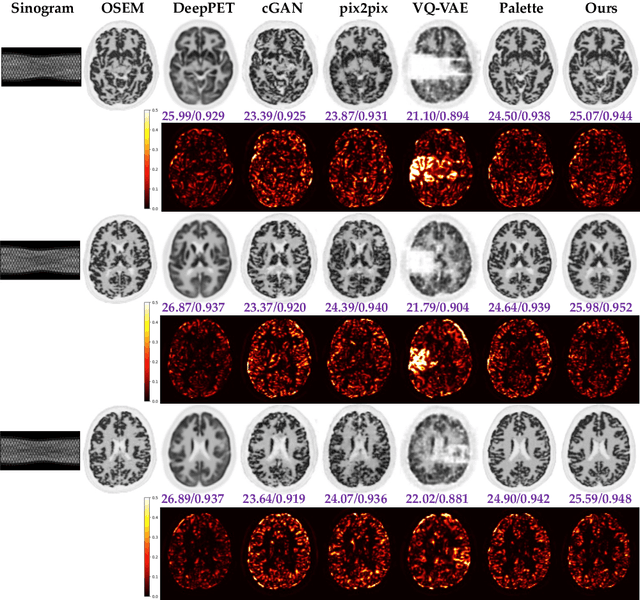

Abstract:Positron Emission Tomography (PET) is a functional imaging modality that enables the visualization of biochemical and physiological processes across various tissues. Recently, deep learning (DL)-based methods have demonstrated significant progress in directly mapping sinograms to PET images. However, regression-based DL models often yield overly smoothed reconstructions lacking of details (i.e., low distortion, low perceptual quality), whereas GAN-based and likelihood-based posterior sampling models tend to introduce undesirable artifacts in predictions (i.e., high distortion, high perceptual quality), limiting their clinical applicability. To achieve a robust perception-distortion tradeoff, we propose Posterior-Mean Denoising Diffusion Model (PMDM-PET), a novel approach that builds upon a recently established mathematical theory to explore the closed-form expression of perception-distortion function in diffusion model space for PET image reconstruction from sinograms. Specifically, PMDM-PET first obtained posterior-mean PET predictions under minimum mean square error (MSE), then optimally transports the distribution of them to the ground-truth PET images distribution. Experimental results demonstrate that PMDM-PET not only generates realistic PET images with possible minimum distortion and optimal perceptual quality but also outperforms five recent state-of-the-art (SOTA) DL baselines in both qualitative visual inspection and quantitative pixel-wise metrics PSNR (dB)/SSIM/NRMSE.

Abstract:Positron emission tomography (PET) is widely utilized for cancer detection due to its ability to visualize functional and biological processes in vivo. PET images are usually reconstructed from histogrammed raw data (sinograms) using traditional iterative techniques (e.g., OSEM, MLEM). Recently, deep learning (DL) methods have shown promise by directly mapping raw sinogram data to PET images. However, DL approaches that are regression-based or GAN-based often produce overly smoothed images or introduce various artifacts respectively. Image-conditioned diffusion probabilistic models (cDPMs) are another class of likelihood-based DL techniques capable of generating highly realistic and controllable images. While cDPMs have notable strengths, they still face challenges such as maintain correspondence and consistency between input and output images when they are from different domains (e.g., sinogram vs. image domain) as well as slow convergence rates. To address these limitations, we introduce LegoPET, a hierarchical feature guided conditional diffusion model for high-perceptual quality PET image reconstruction from sinograms. We conducted several experiments demonstrating that LegoPET not only improves the performance of cDPMs but also surpasses recent DL-based PET image reconstruction techniques in terms of visual quality and pixel-level PSNR/SSIM metrics. Our code is available at https://github.com/yransun/LegoPET.